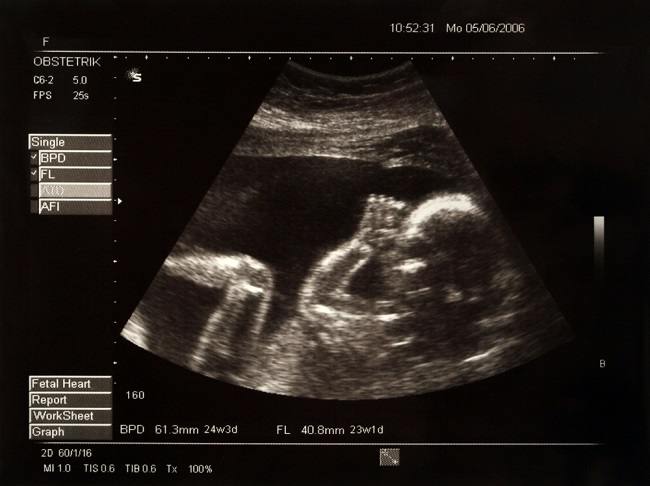

RIAUMANDIRI.ID - Banyak pasangan suami istri datang ke dokter kandungan untuk menanyakan cara memilih jenis kelamin bayi mereka. Alasannya bisa karena ingin meneruskan nama keluarga atau ingin jenis kelamin yang berbeda dengan anak sebelumnya.

Di dunia kedokteran, metode dan teknik pemilihan jenis kelamin telah banyak mengalami perkembangan dari waktu ke waktu. Pemilihan jenis kelamin bayi ini bisa dilakukan dengan metode alami maupun dengan bantuan medis. Namun, apa pun metodenya, jenis kelamin bayi tetap saja bisa tidak sesuai dengan yang diinginkan.

Pemilihan jenis kelamin bayi dilakukan sebelum proses pembuahan. Caranya adalah dengan mengisolasi sperma pembawa kromosom X dan sperma pembawa kromosom Y sebelum membuahi sel telur, agar jenis kelamin bayi hasil pembuahan dapat diatur.

Sperma dapat membawa kromosom X atau Y, sedangkan telur hanya membawa kromosom X. Bila sel telur dibuahi oleh sperma pembawa kromosom X, hasilnya adalah anak perempuan. Namun bila sel telur dibuahi oleh sperma pembawa kromosom Y, jadilah anak laki-laki.

Pemilahan sperma bertujuan untuk menghasilkan sampel air mani dengan proporsi sperma X yang lebih banyak atau sperma Y yang lebih banyak. Dengan begitu, peluang untuk mendapatkan jenis kelamin yang diinginkan akan meningkat.